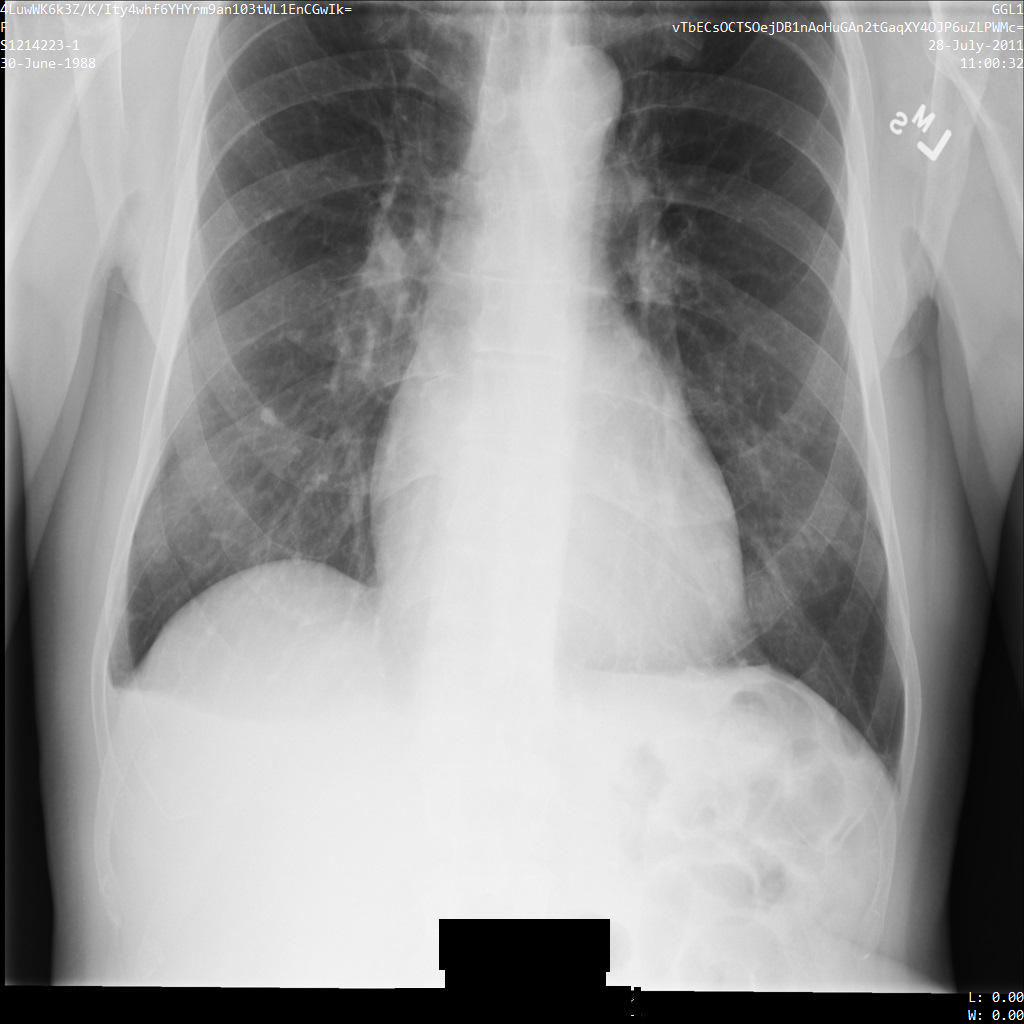

En la siguiente imagen, se muestra una radiografía sin ocultamiento de un paciente:

Después de enviar la imagen a la API de Cloud Healthcare mediante la opción REDACT_SENSITIVE_TEXT, la imagen aparece de la siguiente manera:

Puedes ver que ocurrió lo siguiente:

- Se ocultó el elemento

PERSON_NAMEen la esquina inferior izquierda de la imagen - Se ocultó el elemento

DATEen la esquina inferior izquierda de la imagen

El sexo del paciente no se ocultó porque no se considera texto sensible de acuerdo con los Infotipos de DICOM predeterminados.